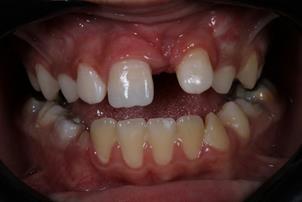

Paciente do sexo masculino, 8 anos de idade, compareceu ao Pronto Atendimento Odontológico Infantil da Clínica de Especialidades Infantis-Bebê-Clínica da Universidade Estadual de Londrina, para tratamento imediato após fratura no incisivo central superior direito devido a queda durante atividade esportiva escolar. Ao exame físico intrabucal, foi diagnosticada fratura coronária do esmalte e da dentina sem comprometimento do tecido pulpar (Figura 1). A resposta ao teste de percussão vertical e horizontal não foi sugestiva de alterações endodôntica e periodontal, respectivamente, e o comprometimento da inserção periodontal também foi descartado por meio do teste de mobilidade no sentido vestíbulo palatino. O exame radiográfico (Figura 2) ratificou o não comprometimento periodontal e periapical, bem como, a não fratura radicular.